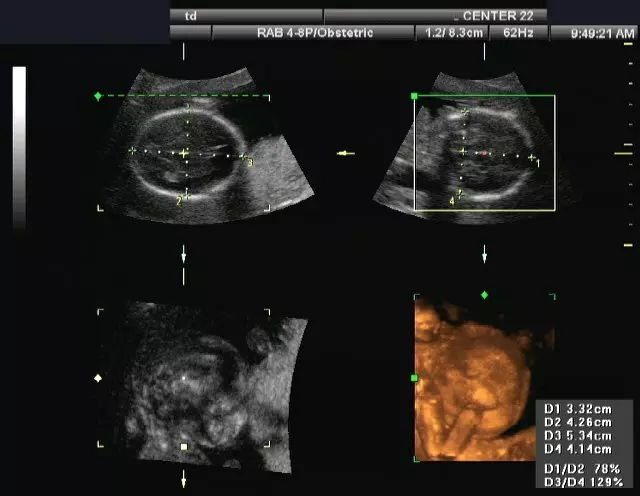

Kompletni ultrazvučni pregled može se obaviti u ordinaciji Hećimović.